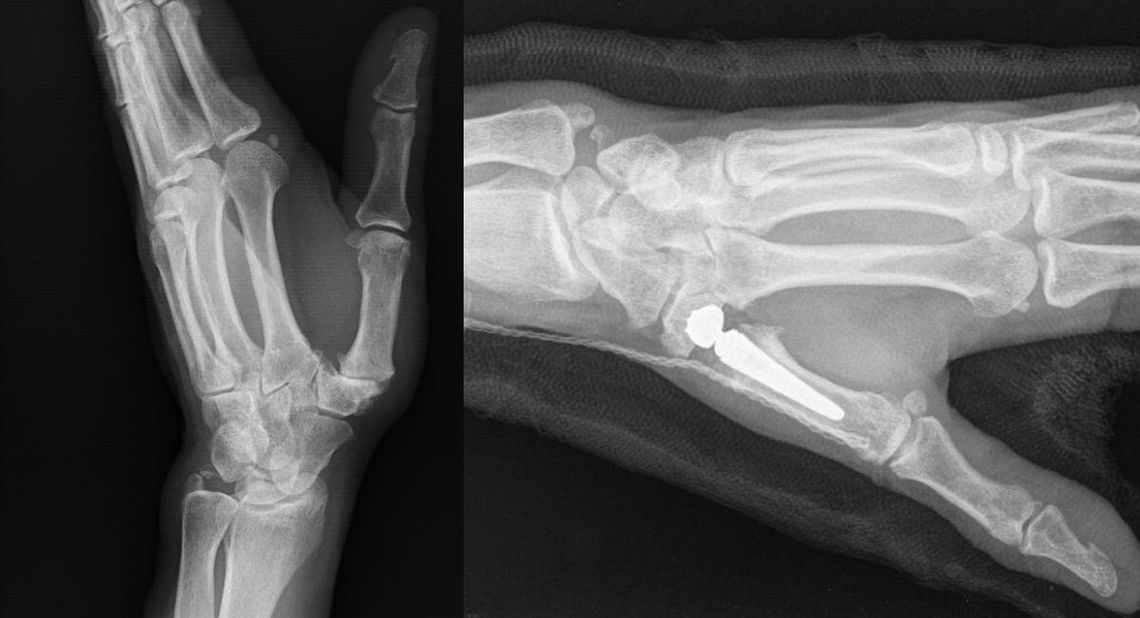

Na czym polega zabieg?

Staw zastępowany jest endoprotezą, co pozwala:

Dzięki nowoczesnej technice i implantom Touch CMC I pełna ruchomość ręki wraca już po ok. 6 tygodniach!

Proteza jest dwumobilna, co oznacza, że: zapewnia naturalny ruch w dwóch miejscach, gwarantuje pełną stabilność i minimalizuje ryzyko zwichnięcia.